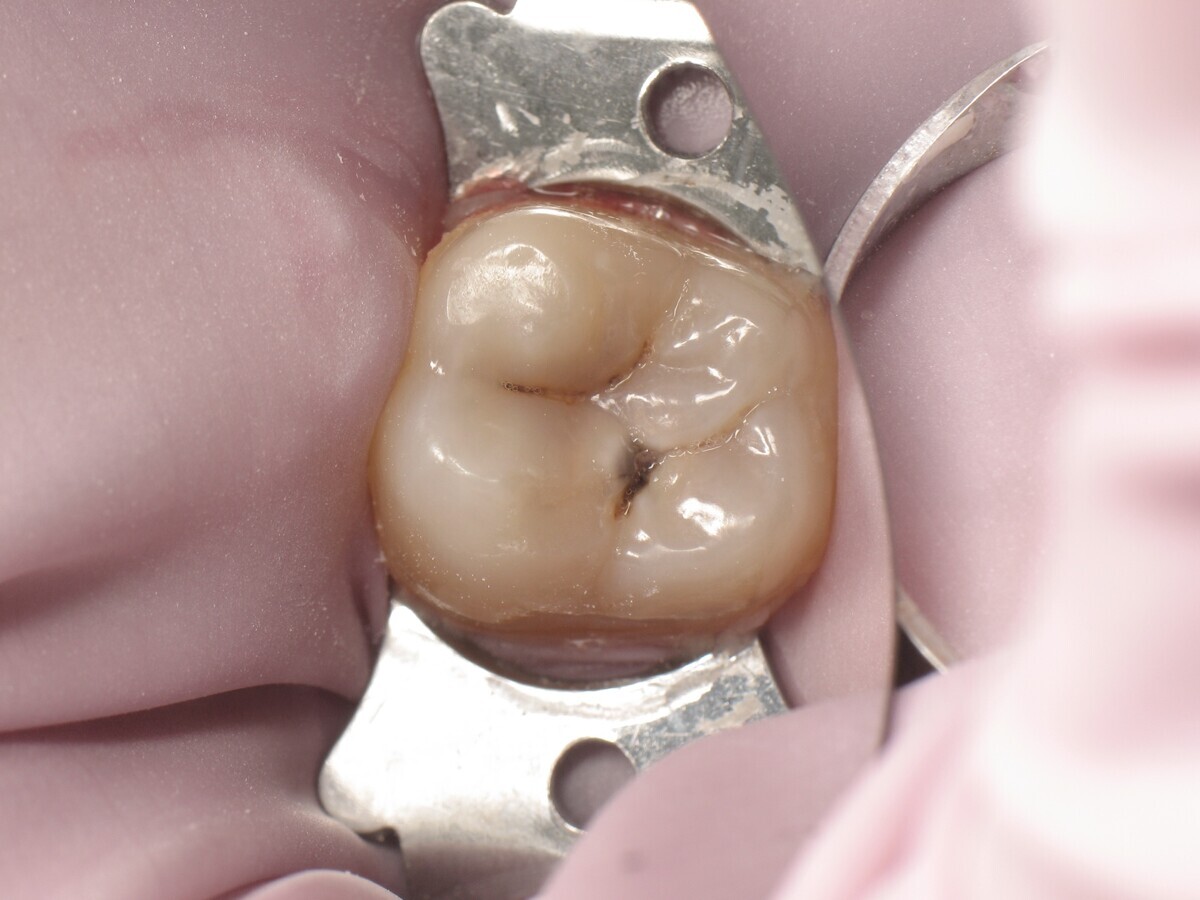

Este artículo describe el tratamiento de una cavidad clase I en un molar utilizando un composite termoviscoso mediante la técnica de la almohadilla (Figura 1). En primer lugar, se registran los detalles anatómicos utilizando una resina transparente, fluida y fotopolimerizable (Clip Flow, VOCO). El diente se aísla con un dique antes de aplicar el composite transparente a la superficie oclusal con un cepillo aplicador y fotopolimerizar durante 10 segundos (Figuras 2-4). La almohadilla oclusal así obtenida (Figura 5) debe almacenarse en alcohol (etanol o isopropanol) para eliminar la capa de inhibición. Luego se limpia la cavidad clase I (Figuras 6 y 7). A continuación se graba el esmalte durante 30 segundos y la dentina durante 15 segundos (Conditioner 36, Dentsply Sirona) y luego se enjuaga bien (Figuras 8 a 10). Debido al bajo espesor de la dentina remanente, también se aplica protección pulpar (Telio Desensitizer, Ivoclar Vivadent) (Figura 11). Luego se frota el adhesivo sobre las superficies dentales durante 20 segundos (Futurabond DC, VOCO), luego se seca bajo una pulverización de aire sin aceite graso durante 5 segundos y luego se fotopolimeriza durante 10 segundos (Figuras 12, 13). Para una humectación óptima, el fondo de la cavidad se cubre con un compuesto fluido de baja viscosidad (GrandioSO Light Flow, A3.5, VOCO) y se fotopolimeriza durante 20 segundos (Figuras 14, 15). Utilizando el Dispensador VisCalor, un dispensador portátil que permite el calentamiento y la aplicación simultánea de resinas, la cavidad se llena luego con un composite termoviscoso bulk (VisCalor Bulk, A2, VOCO).

Figura 01. Molar con caries clase I.

Figura 06. Cavidad durante la excavación.

Figura 07. Cavidad después de la excavación.